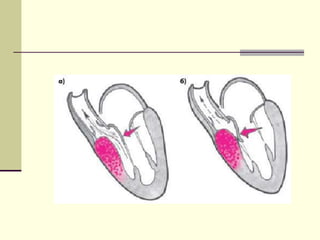

Дилятационная миокардиопатия

 Дилятационная миокардиопатия – это

хроническое заболевание мышцы сердца,

характеризующееся дилятацией левого

желудочка с нарушением его

систолической функции и быстрым

развитием застойной сердечной

недостаточности.

 Заболеваемость 20 : 100000 (1:5000).

Гипертрофическая миокардиопатия – это

частое генетическое расстройство (1:500),

проявляющееся левожелудочковой гипертрофией

при отсутствии системных причин ее

возникновения. Наблюдается во всех расах и

поражает в равной степени мужчин и женщин.